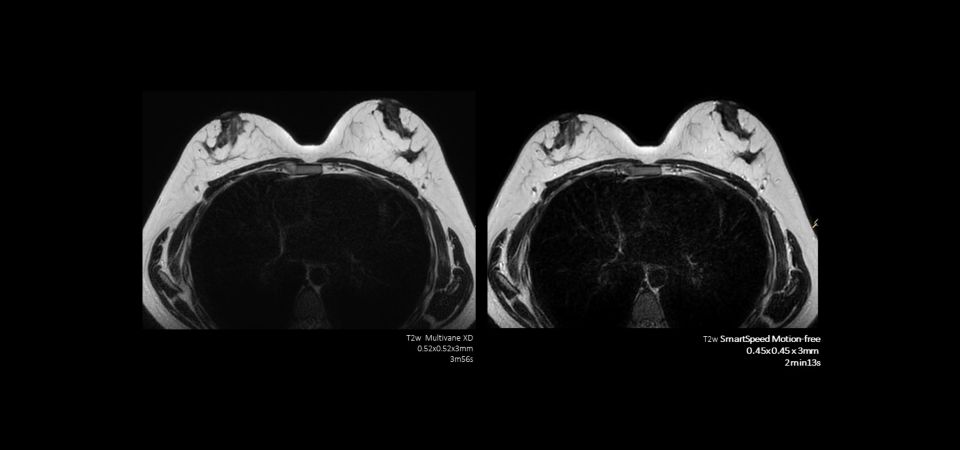

Philips SmartSpeed delivers fast high-quality imaging for wider range of patients including patients who are in pain, struggling to hold still. Philips SmartSpeed MotionFree utilizes non-Cartesian, motion robust 2D imaging techniques to acquire fast, motion-free body images. It reduces gross motion, breathing motion and pulsatility artifacts in over 90% of the cases compared to Cartesian imaging.